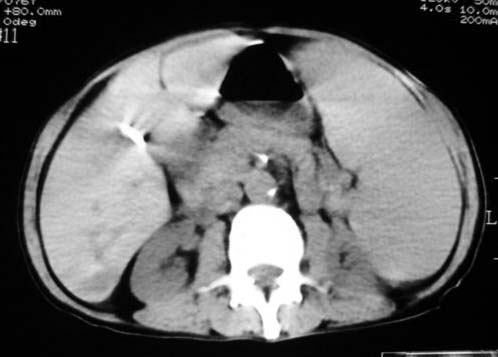

以下是引用dyqct在2007-4-20 16:38:00的发言:[br]考虑:1、巨脾;[br] 2、肝内多发低密度,首先考虑转移瘤;[br] 3、胆囊多发结石。